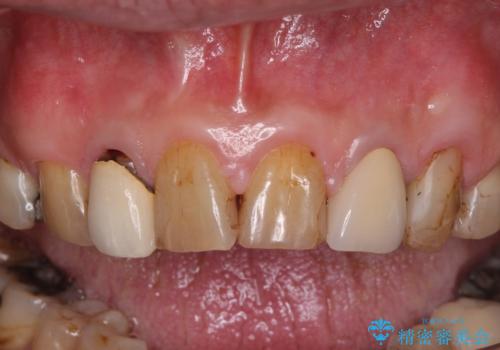

- コンポジットレジンやクラウンなど、様々な医院で治療を受けたために、統一感がなくなってしまった前歯を綺麗にしたいとのことで来院された患者様です。

黄ばんだ前歯や白すぎたクラウン、プラスチックの継ぎ接ぎなどを全てオールセラミッククラウンの統一感のある前歯に仕上げました。